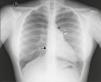

Chest X‐ray: displacement of the cardiac silhouette to the left without tracheal deviation, obliteration of the right cardiac border overlapping the spine and imprint of the pulmonary artery (Figure 2).

Figure 2.Posterior–anterior chest X‐ray showing levoposition of the heart without tracheal deviation, right heart border superimposed on the spine (straight arrow), imprint of the main pulmonary artery (curved arrow), interposition of lung parenchyma between the aortic arch and left pulmonary artery (asterisk) and flattening and elongation of the left ventricular contour (Snoopy sign).